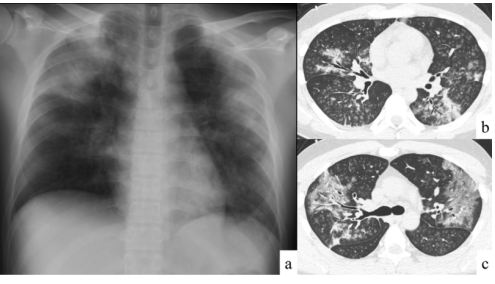

现患者发热,咳嗽感胸痛伴胸闷,咳黄白色黏痰,无恶心呕吐,无头晕头痛等不适。查体:两肺呼吸音粗,右肺可闻及干/湿啰音。2021年4月10日肺部CT示:两肺多发斑片磨玻璃影及间质改变(图1)

图片

图1 患者胸部CT(2021-04-10)